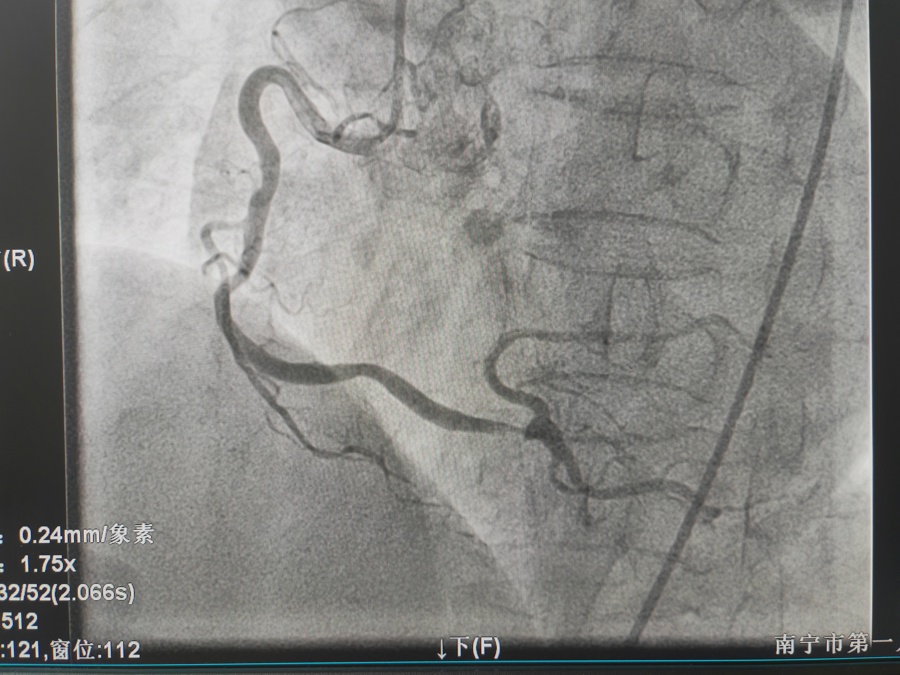

冠心病的治疗

冠脉支架置入术是将以不锈钢或合金材料刻制或绕制成管状而其管壁星网状带有间隙的支架(药物支架),置入冠状动脉内已经或未经PTCA扩张的狭容节段支撑血管壁,维持血流畅通。因球囊扩张后,约20-40%的病变会发生再狭窄,有些会发生急性冠脉闭塞而导致急性心肌梗死或死亡,所以在扩张后,多致需要再用冠脉内支架将病变处永久性撑开,即支架置入。置入支架是为了减少斑块撕袭后塌陷,急性塞,增加手术安全性,减少再狭窄。目前PTCA加上支架置入术已成为治疗冠心病的重要手段。